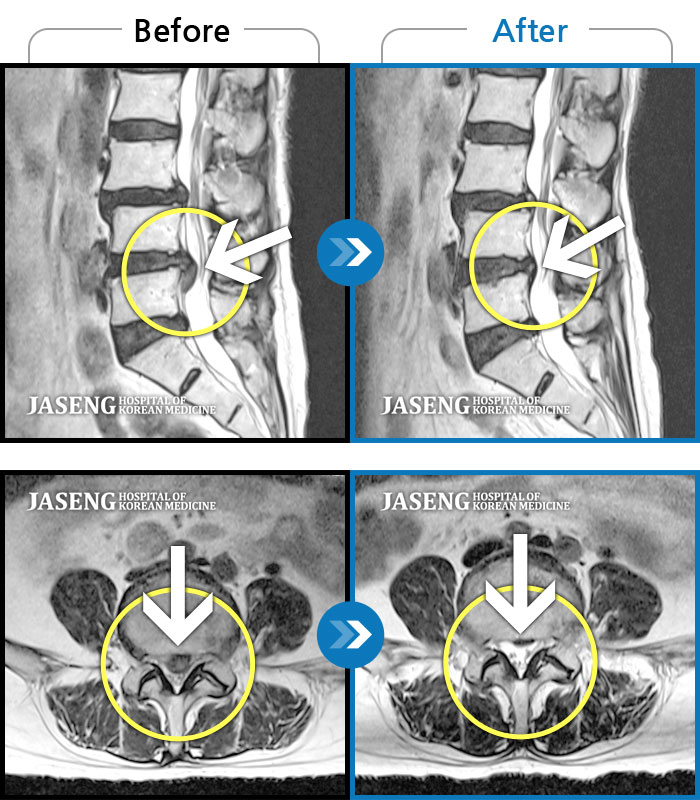

Before

After

환자에게 사전 동의를 받아 동일 조건에서 촬영되었습니다.

개인에 따라 치료 후 부작용이 발생할 수 있으니 의료진과 상담 후 치료를 진행하시기 바랍니다.

하요추부 통증, 자가보행이 어렵고 좌측 대퇴부 견인통

앉았다 일어날때 통증, 허리 당김